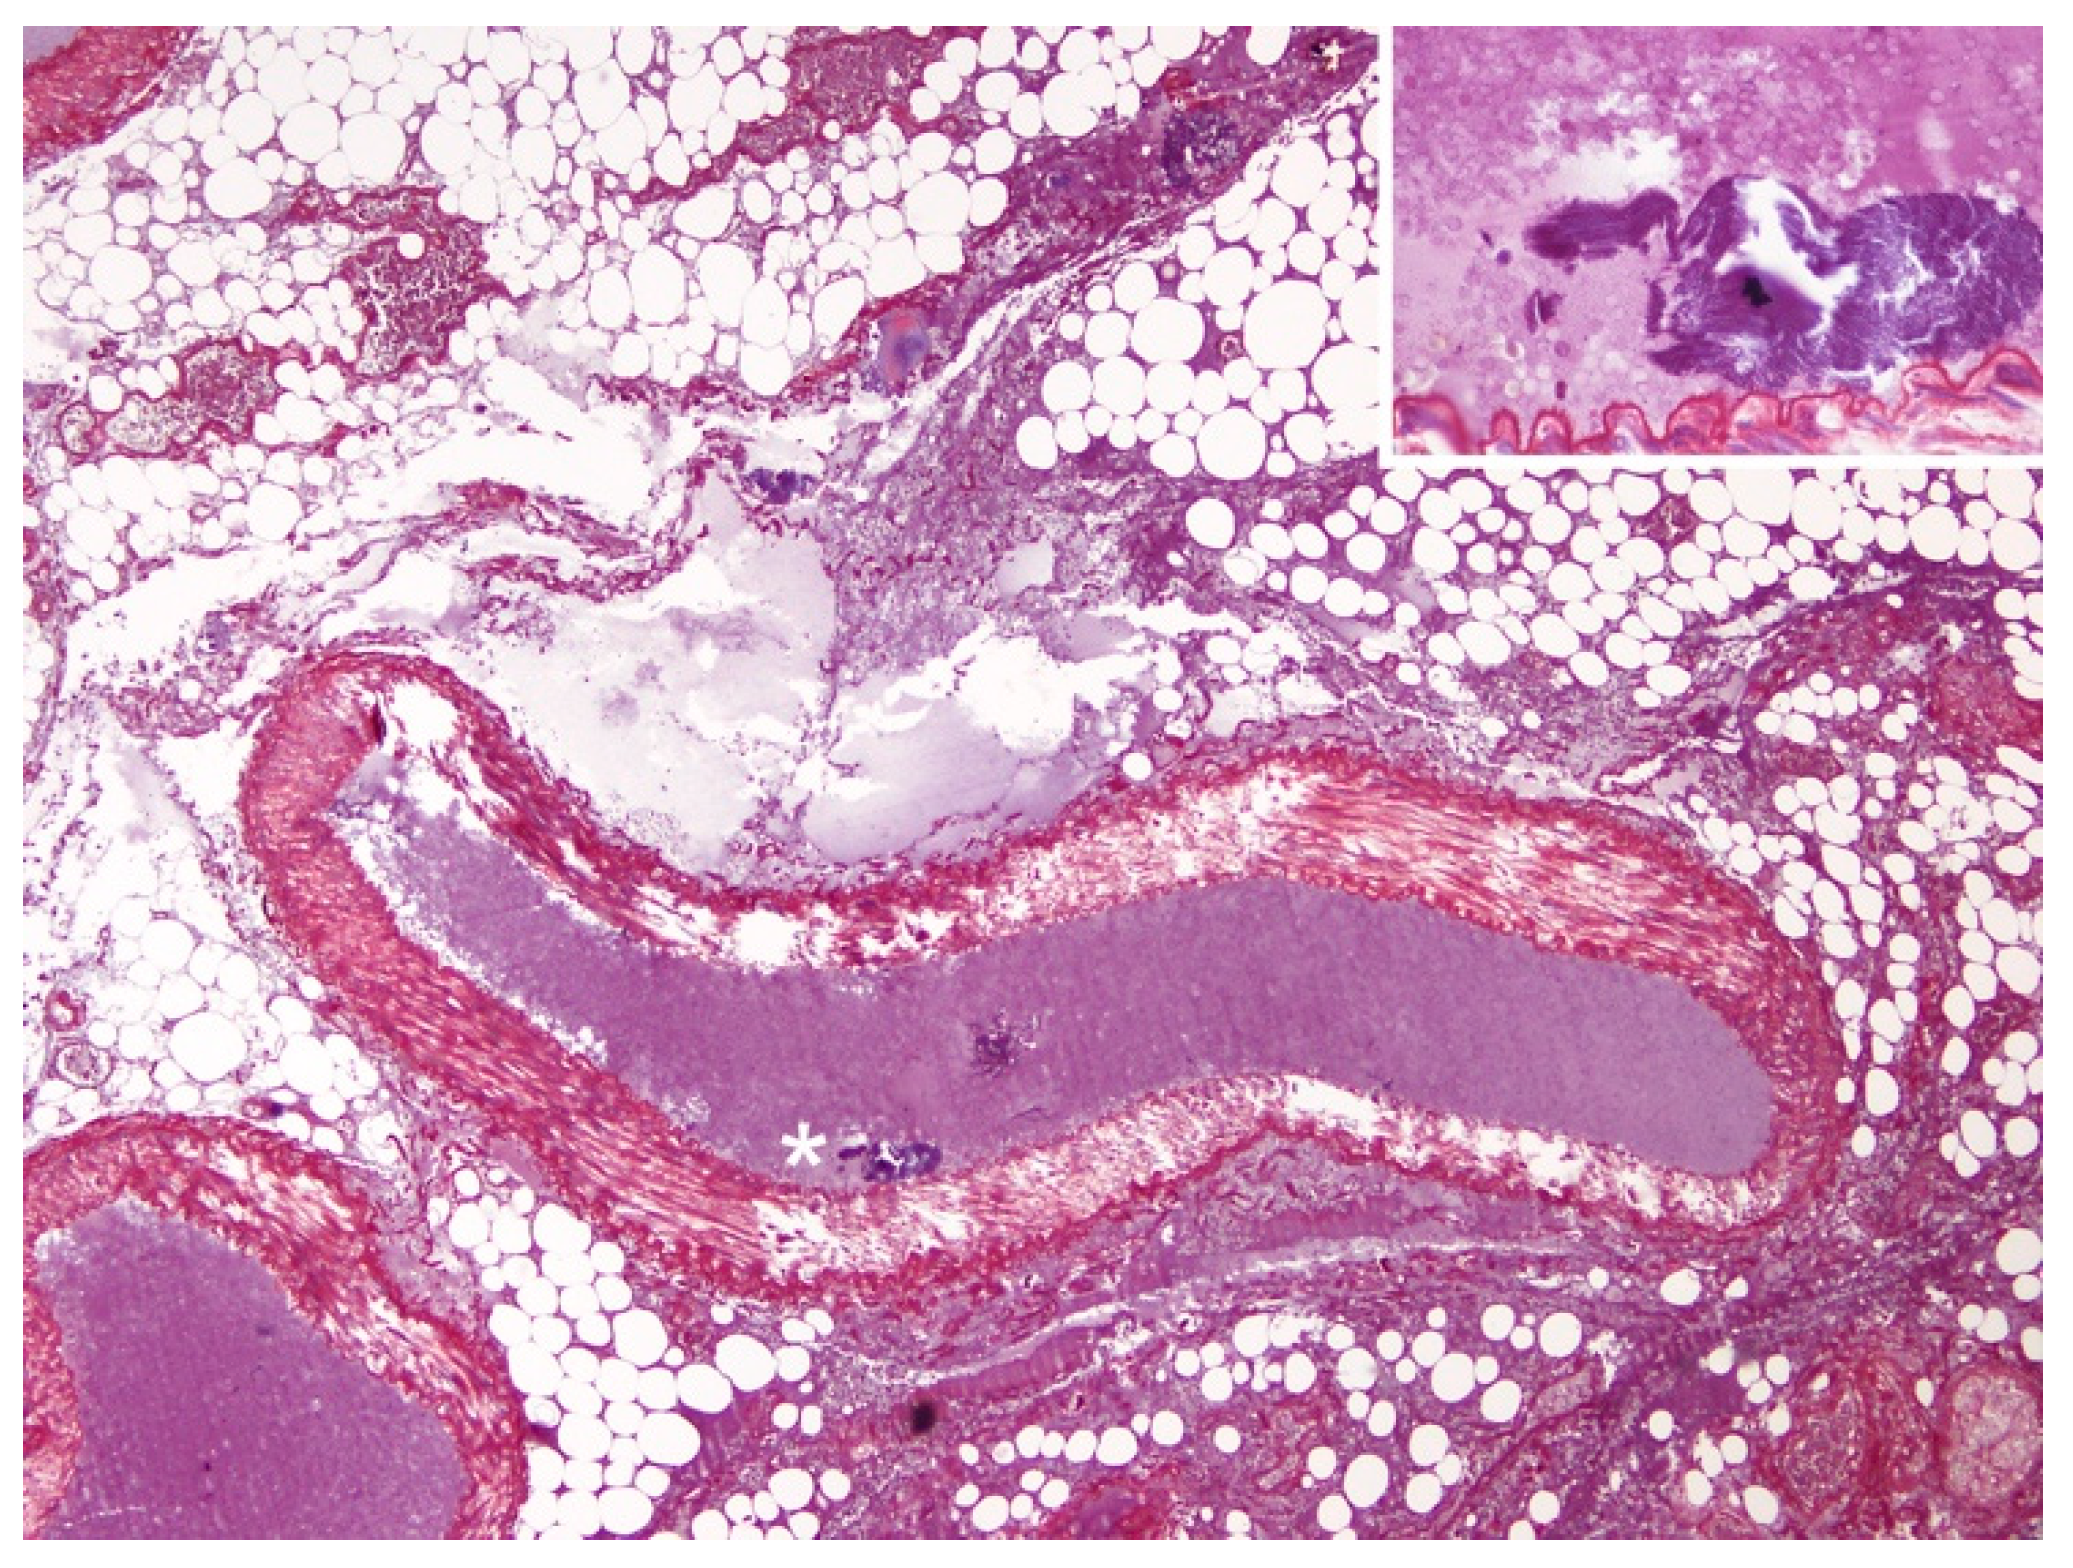

3.2. Histopathological and Histochemical Findings

3.3. Immunohistochemical Findings